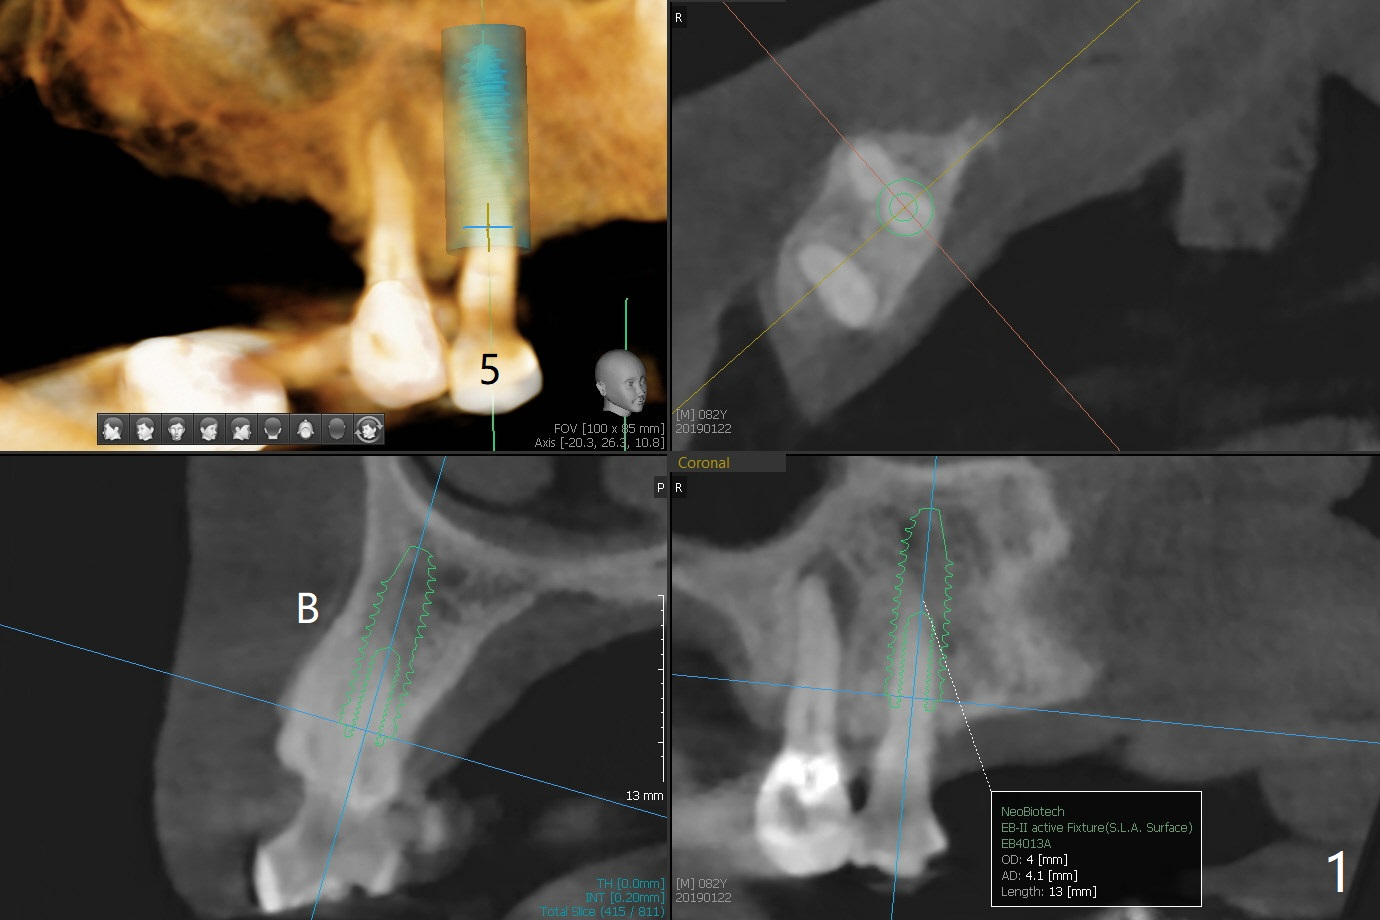

Root canal therapy of the tooth #5 of a 84-year-old man failed due to the obliterated canal ~2 years earlier (Fig.1). He requests extraction and implant (IS) to retain the mobile upper RPD. PRF is prepared to repair the apical lesion. Take photos of the latter before surgery. Make sure no leakage of bone graft, including suture, multiple reline and perio dressing.